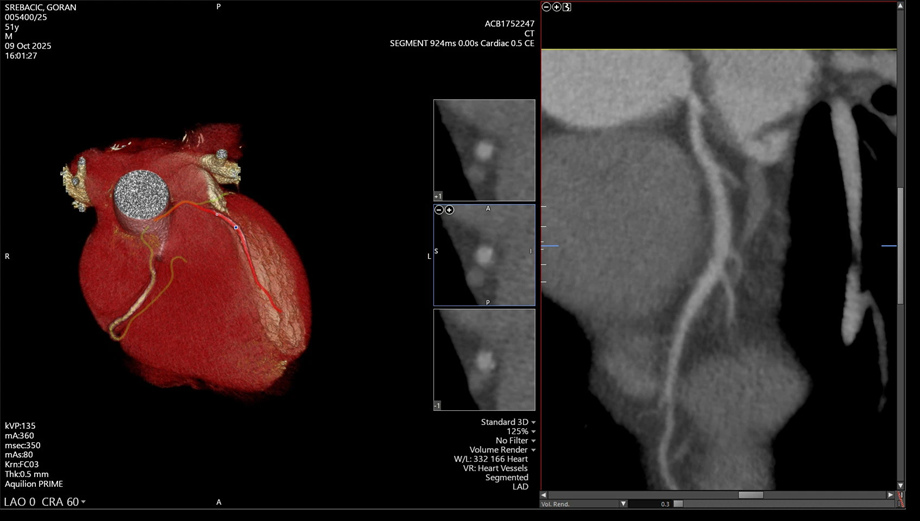

Upravo zato preventivne pretrage, poput MSCT koronarografije i Calcium scoringa, koje su nedavno uvedene u ponudu Medicinskog centra Gorica, imaju iznimno važnu ulogu u ranom otkrivanju bolesti srca i krvnih žila te s razlogom ističemo kako spašavaju živote.

MSCT koronarografija je neinvazivna metoda prikaza srčanih arterija koja se danas smatra zlatnim standardom u ranom otkrivanju bolesti srca. Ova najmodernija radiološka pretraga omogućuje preciznu procjenu suženja i začepljenja koronarnih arterija bez potrebe za invazivnim zahvatom poput uvođenja katetera u krvne žile. Pretraga traje svega nekoliko minuta, a rezultati su izuzetno pouzdani.

Calcium scoring je probirna metoda kojom se mjeri količina kalcija u stijenkama krvnih žila. Budući da nakupljanje kalcija označava prisutnost ateroskleroze, ova pretraga omogućuje brzu procjenu kardiovaskularnog rizika, odnosno rizika od srčanog udara. Često se izvodi samostalno ili u kombinaciji s MSCT koronarografijom.

„Nažalost, mnogi ljudi s navedenim rizičnim čimbenicima nemaju ikakve tegobe dok ne dožive srčani udar. MSCT koronarografija omogućuje nam da bolest otkrijemo na vrijeme – bezbolno i sigurno. Ova pretraga predstavlja vrhunac suvremene radiološke dijagnostike i iskreno smo ponosni što je možemo ponuditi našim sugrađanima. Dosadašnje snimke pokazale su iznimnu kvalitetu i preciznost. Kad smo tek uveli ovu pretragu, dvoje od prvih deset pacijenata, koji nisu imali nikakve simptome, imalo je kritično suženje koronarne arterije. Riječ je o osobama koje su bile u predinfarktnom stanju, a da toga nisu bile svjesne. Upravo takvi slučajevi pokazuju koliku vrijednost ima ova pretraga – ona doslovno spašava živote“, izjavio je dr. sc. Nikola Ivan Leder, ravnatelj Medicinskog centra Gorica.

Ove suvremene dijagnostičke metode omogućuju preciznu procjenu stanja koronarnih arterija i procjenu rizika od kardiovaskularnih bolesti — često i prije pojave prvih simptoma.